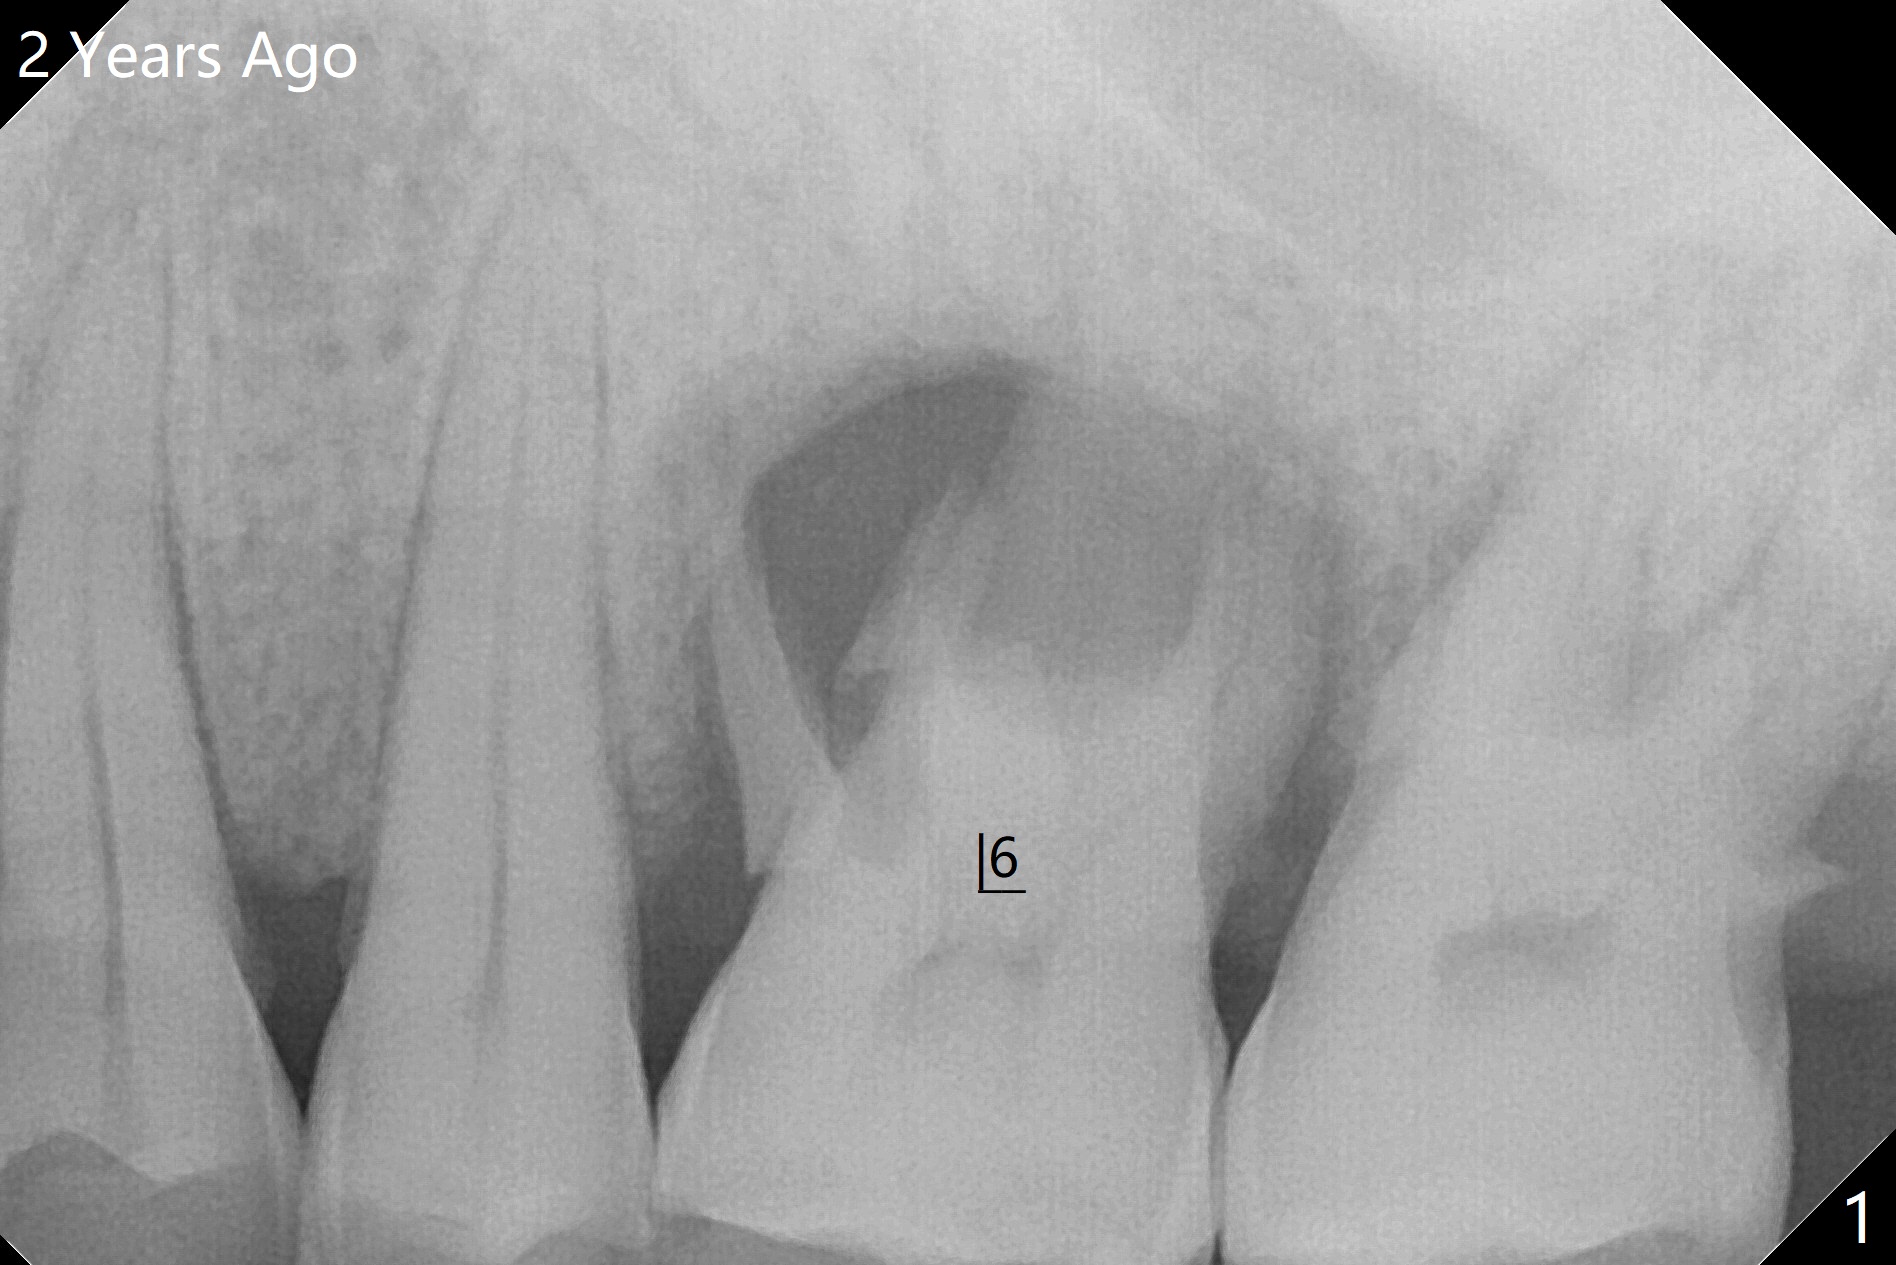

50岁男两年前不肯拔牙左上6(图一),现在要求及早拔除植骨(图二),几个月后与左下7一起植牙。我们准备深洗(图三橘黄色)后拔除残根(黑色),翻瓣后植入粘性骨块(红色)。为了解释手术步骤,给牙槽骨(A)做冠状切面,如图四黑色四方形,B:颊侧;P:腭侧;而粉红色代表牙龈(G)。图五红线表示切口,弯箭头:翻瓣,如图六。然后植入粘性骨块(图七:S)。盖上PRF膜(图八蓝线)以及不可吸收膜(图八绿线),最后使用PTFE缝线(图九:黑线)稍微关闭伤口,不至于压扁骨块。这样可行吗?需要使用tenting screw防止骨块塌陷?为了避免使用后者,索性直接植入植体(图十:绿色)和基台(浅蓝色),周围堆放骨粉(红色)。覆盖PRF膜(图十一:深蓝色),缝合(细线)。骨密度1200-1400单位;骨粘膜厚度4.2毫米,血供好(图十二;图十三:G: 牙龈)。翻瓣(图十四:箭头),植入植体(绿色),放置基台(粉红色)和骨粉(红色)。由于基台占据空间,缝合应该是松弛的,下面骨粉不易移位,在暴露螺纹附近愈合。Jennifer: flap surgery; since osteotomy will be created in a slope with most likely distal deviation, design the long axis of the implant mesial by 1 mm occlusally.